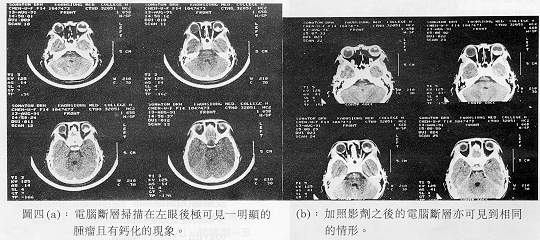

液循環(Double circulation),在晚期則有大量螢光劑滲出的現象(圖二)。眼部超音波檢查在A scan顯示有高腫瘤內反射(High internal reflectivity),B scan則顯示在後極(posterior pole)有一很大的腫瘤且合併視網膜剝離(圖三)。電腦斷層掃描在左眼後極可見一明顯的腫瘤且有鈣化的現象(圖四)。